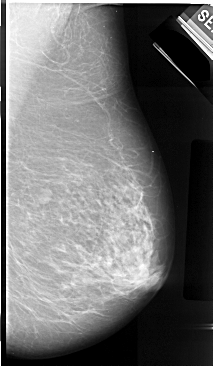

A_1065_1.LEFT_MLO

LEFT_CC LINES 5416 PIXELS_PER_LINE 2911 BITS_PER_PIXEL 16 RESOLUTION 42 NON_OVERLAY